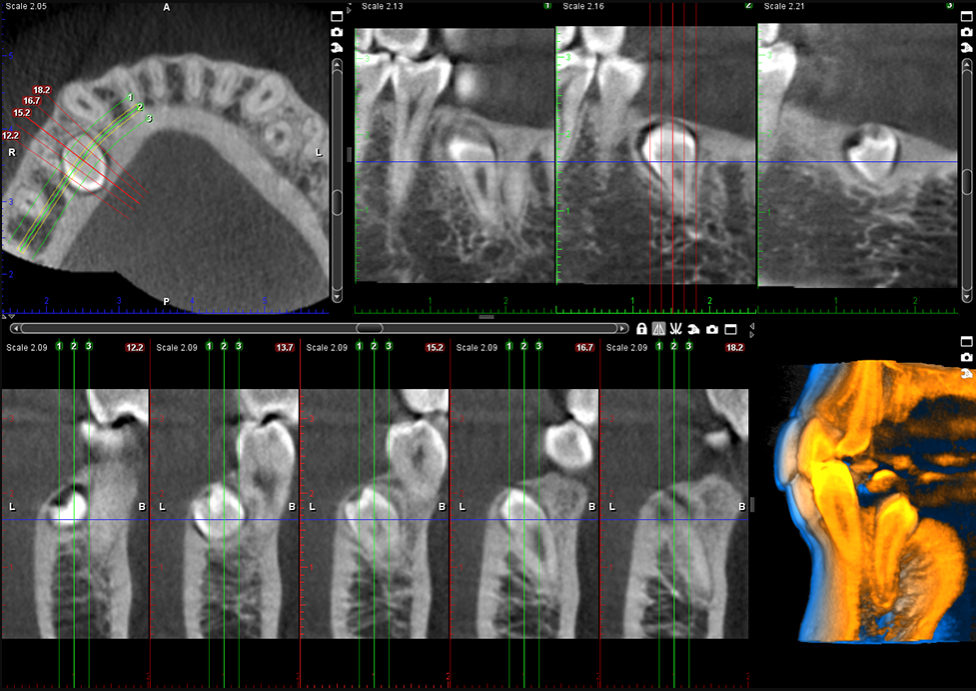

Planmeca ProSensor® intraoral sensörümüz, eşsiz görüntü kalitesi, ileri seviye hasta merkezli tasarım ve gelişmiş kullanılabilirlik özelliklerin benzersiz bir kombinasyonunu sunar. Dijital sensör uzun ömürlü olacak şekilde tasarlandı. Güvenilebilecek bir sağlam kullanım sunar.